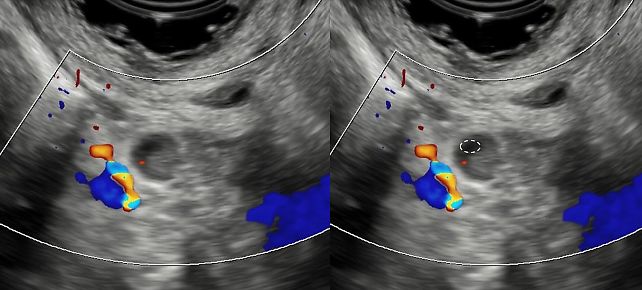

Vascularization (assessed by Doppler imaging)

- Normal/reactive nodes

- central vascular flow limited to the hilum

- regular, symmetric branching pattern

- Suspicious/malignant nodes

- peripheral or mixed vascularity (Figure 16)

- transcapsular flow (vessels penetrating from the periphery towards the center) suggesting tumor infiltration

- chaotic blood flow on power Doppler

16

Pelvic node with mixed vascularization, visualized with a convex probe.